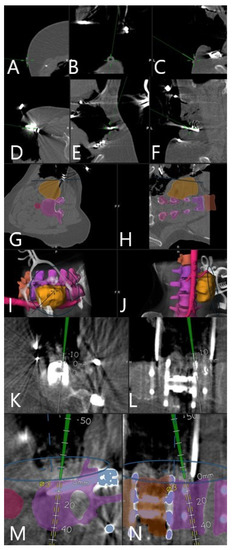

3.4. Augmented Reality

3.5. Clinical Application of iCT and AR